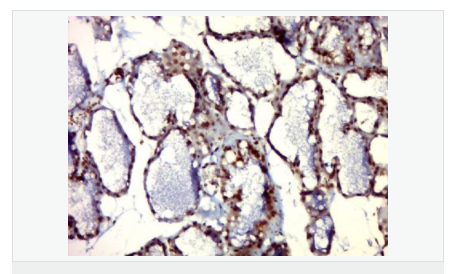

image.png